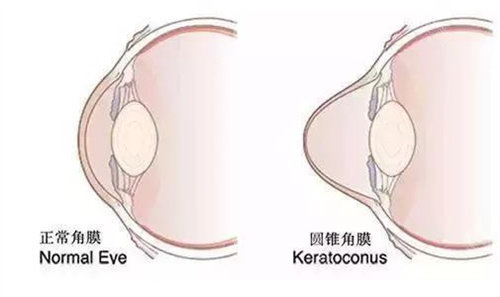

角膜病正规是科室的特色之一,对于各种角膜疾病,如角膜炎、角膜溃疡等,有着丰富的诊断和治疗经验。